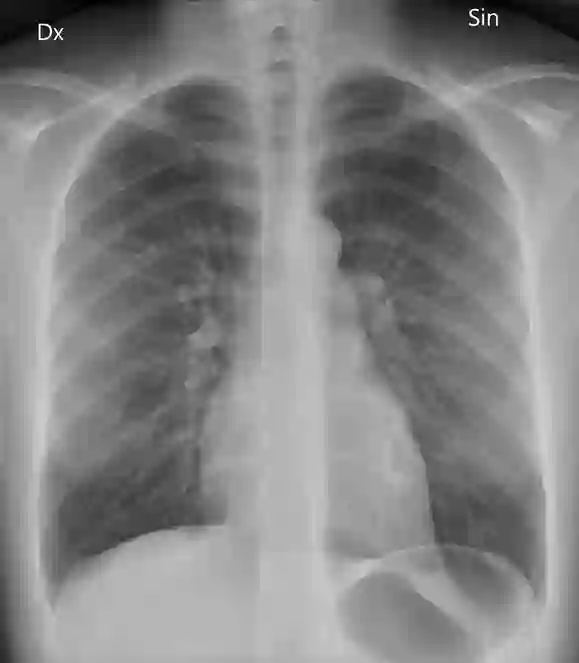

Artificial intelligence in healthcare requires models that are accurate and interpretable. We advance mechanistic interpretability in medical vision by applying Medical Sparse Autoencoders (MedSAEs) to the latent space of MedCLIP, a vision-language model trained on chest radiographs and reports. To quantify interpretability, we propose an evaluation framework that combines correlation metrics, entropy analyzes, and automated neuron naming via the MedGEMMA foundation model. Experiments on the CheXpert dataset show that MedSAE neurons achieve higher monosemanticity and interpretability than raw MedCLIP features. Our findings bridge high-performing medical AI and transparency, offering a scalable step toward clinically reliable representations.